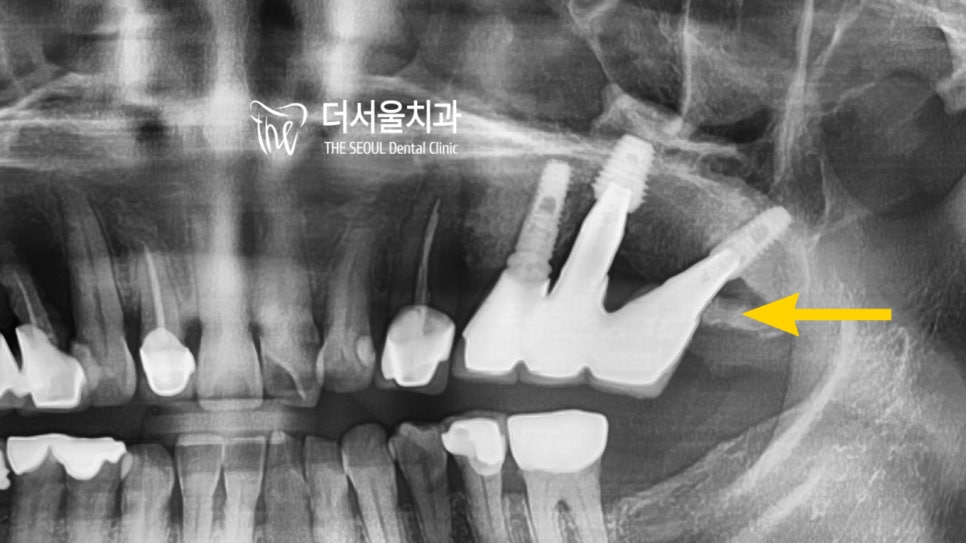

문제는 반대편에 존재하고 있었는데요.

20번대 치아를 보면 다트를 꼽아놓은 듯

주변 조직이나 치축, 방향들을 고려하지 않고

그냥 심어놓은 고정체를 확인할 수 있습니다.

정말.. 같은 의료진이지만 화가 나더라고요..ㅎㅎㅠㅠ

이렇게 삐뚤게 심어진 것은

염증이 생기기 쉽고 잘 부을 수 있습니다.

또한 추후에 있을 A/S가 어려워지게 되죠.

20번대의 경우는 염증으로 인해 고름도 생기고

치조골 소실이 심한 상태였는데요.